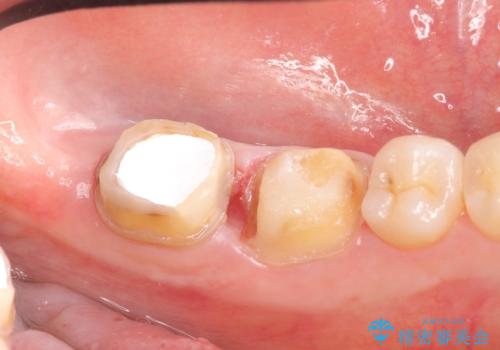

- 左下奥歯で咬むと違和感があるといらっしゃった方の症例です。

検査の結果左下7は失活(歯の神経が死んでいること)しておりX線上で根尖病変を認めたため、根管治療を行いました。

また左下6は遠心にあった歯茎より深い虫歯(縁下カリエス)の問題を解決するため、歯茎を下げる歯周外科手術を行いました。